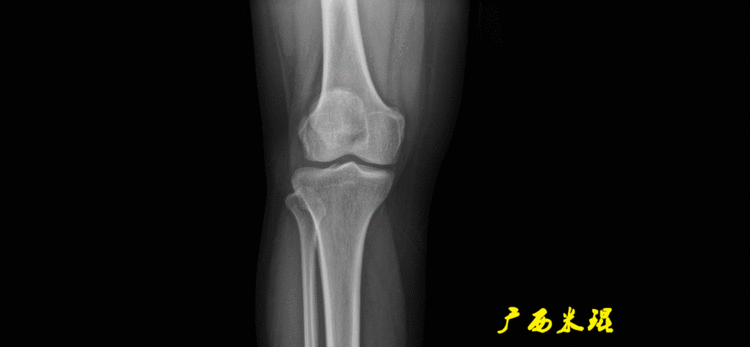

(2)膝关节中心膝关节中心点常用的有5个不同的定位方法,分别是股骨髁中点、股骨髁间窝顶点、膝关节间隙水平软组织中点、胫骨髁间嵴中点和胫骨平台中点,我们可以根据具体情况来选用。

(2)股骨远端关节线正位为股骨内外侧髁最低点之间的连线。髌骨下极在此线之上,距离大于20mm可考虑为高位髌骨。

(3)胫骨近端关节线正位为胫骨内外侧平台最低点之间的连线。

股骨远端外侧角(mLDFA):股骨内外侧髁远端切线(关节线)与股骨头和膝关节中心的连线(机械轴)两者之间形成的外侧夹角,正常为87°±3°。

胫骨近端内侧角(mMPTA):胫骨内外侧平台切线(关节线)与股骨头和膝关节中心的连线(机械轴)两者之间形成的内侧夹角,正常为87°±3°。

5、画出与解剖轴相关的角度解剖股胫角(aFTA):股骨干下段轴线(解剖轴)与胫骨上段轴线(解剖轴)在膝关节所形成的夹角,正常为174°±1°。膝关节OA的畸形常常由于一侧软组织及关节的过度磨损所致,临床多为内侧磨损过度,因此表现为轻度膝内翻畸形,X线表现为解剖股胫角小于174°,而胫骨角正常。

解剖股骨远端外侧角(aLDFA):股骨干下段轴线(解剖轴)与股骨内外侧髁远端切线(关节线)在膝关节外侧所形成的夹角,正常为81°±2°。大多数膝外翻患者的畸形发生于股骨下端,表现为股骨远端外侧角小于正常值。

解剖胫骨近端外侧角(也叫aMPTA):胫骨干上段轴线与胫骨平台切线(关节线)在膝关节外侧所形成的夹角,常称为胫骨角,正常为87°±3°。大多数膝内翻患者的畸形发生于胫骨上端,表现为胫骨角大于90°。严重的膝内翻畸形发生在整个下肢,股骨干及胫骨干都有可能形成向内弯曲的弧形。

6、其他角度胫骨股骨关节线夹角(JLCA):胫骨近端关节线与股骨远端关节线之间的夹角,正常生理状态下几乎为0°。当JLCA>2°时提示异常,通常为韧带松弛或者软度磨损丢失所致。